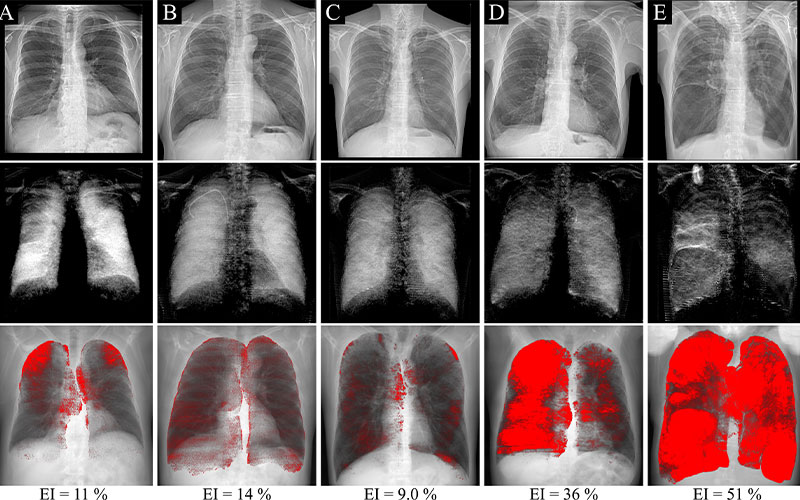

From www.researchgate.net